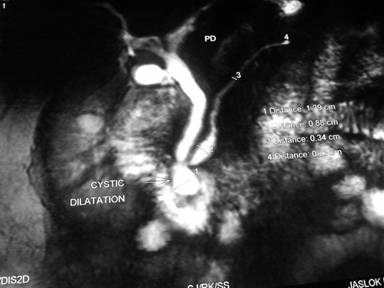

A 63-year-old male had two episodes of acute pancreatitis by biochemistry and abdominal ultrasonography. EUS findings showed an ampullary mass and cystic dilatation of terminal portion of duct of Wirsung suggestive of wirsungocele (Figures 1 and 2). EUS guided FNA from the ampulla suggested a neuroendocrine tumor. MRCP confirmed EUS findings of wirsungocele and ampullary mass (Figure 3). ERCP (Figure 4) and endoscopic ampullectomy was then performed and patient made an uneventful recovery. The histopathological examination and immunohistochemistry showed neuroendocrine tumor (pathological classification: G1) with cells expressing synaptophysin and chromogranin (Figure 5). The Mib proliferation index was less than 2%. The pancreatic duct was seen well dilated within the tumor tissue.

Figure 3. MRCP showing cystic dilation of terminal part of main pancreatic duct. |